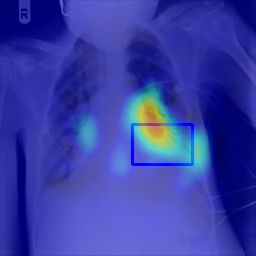

Deployments of artificial intelligence in medical diagnostics mandate not just accuracy and efficacy but also trust, emphasizing the need for explainability in machine decisions. The recent trend in automated medical image diagnostics leans towards the deployment of Transformer-based architectures, credited to their impressive capabilities. Since the self-attention feature of transformers contributes towards identifying crucial regions during the classification process, they enhance the trustability of the methods. However, the complex intricacies of these attention mechanisms may fall short of effectively pinpointing the regions of interest directly influencing AI decisions. Our research endeavors to innovate a unique attention block that underscores the correlation between 'regions' rather than 'pixels'. To address this challenge, we introduce an innovative system grounded in prototype learning, featuring an advanced self-attention mechanism that goes beyond conventional ad-hoc visual explanation techniques by offering comprehensible visual insights. A combined quantitative and qualitative methodological approach was used to demonstrate the effectiveness of the proposed method on the large-scale NIH chest X-ray dataset. Experimental results showed that our proposed method offers a promising direction for explainability, which can lead to the development of more trustable systems, which can facilitate easier and rapid adoption of such technology into routine clinics. The code is available at www.github.com/NUBagcilab/r2r_proto.